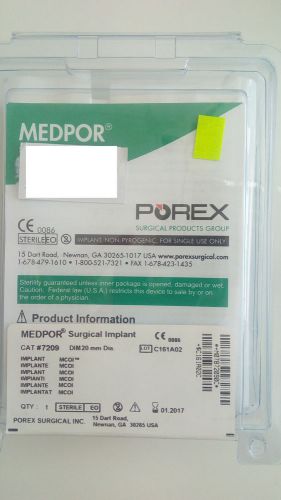

MEDPOR Multipurpose Conical Orbital Implants MCOI 20mm (use by 01/2017)